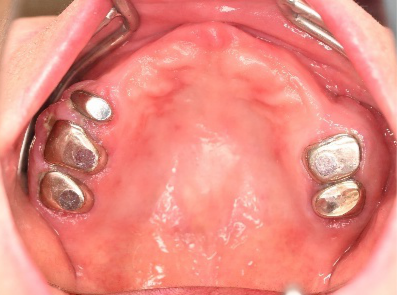

Before

赤丸は抜歯しました。上4本、下3本